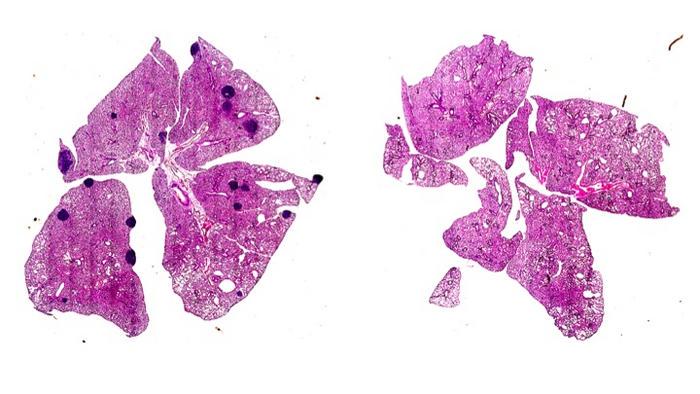

Utilizing a mouse model of melanoma, the researchers demonstrated that aspirin administration led to a marked reduction in the frequency of metastases, affirming their hypothesis that the drug facilitates T cell reactivation against cancer cells by alleviating the suppression previously imposed by TXA2. This synergistic effect highlights the potential of aspirin not just as an analgesic, but as a powerful immunomodulatory agent capable of modifying the landscape of metastatic cancer.

Image Credits: Copyright: Jie Yang